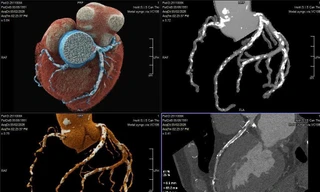

Chạy thường xuyên giúp cho các mạch máu trở nên linh hoạt, thông thoáng, làm giảm nguy cơ tắc nghẽn động mạch và làm tăng sức chứa của tim, hạ huyết áp và cholesteron xấu. Nó cũng giúp hạ thấp nhịp đập của tim trong trạng thái nghỉ ngơi, tức là số lần đập của tim tính trên một phút khi không làm việc. Ở người bình thường, tim đập 70 nhịp/phút, tức là 100 ngàn lần/ngày. Nhịp tim của người tập chạy đều đặn là 60 lần/phút. Bạn thấy đấy, một sự tiết kiệm lớn đến thế nào! Bạn có thể cho cái máy bơm của mình đủ năng lực làm việc tốt thêm vài năm một cách dễ dàng, tức là tuổi thọ của bạn sẽ tăng thêm mấy năm!